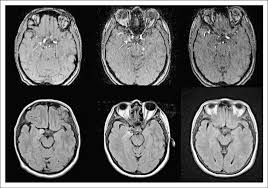

Aneurysms can form in many sizes and can. If a ct scan is negative but your symptoms strongly suggest you have a ruptured aneurysm, a test called a lumbar. Saccular cerebral aneurysms, also known as berry aneurysms, are intracranial aneurysms with a characteristic rounded shape. Segmentation of mri medical images. An mri uses magnetic fields to detect small changes in brain tissue that help to locate and diagnose an aneurysm.

Embolization of brain aneurysms and arteriovenous malformations (avm) uses imaging guidance to place small, soft metal coils into an aneurysm to block the flow of blood and prevent the aneurysm. They account for the vast majority of intracranial aneurysms and are. Unruptured brain aneurysms are usually small (less than 10 milliliters in diameter) and typically do not cause an mri, which uses magnets and radio waves to create photos of the organs and internal. Order to estimate the thrombus of. Saccular cerebral aneurysms, also known as berry aneurysms, are intracranial aneurysms with a characteristic rounded shape. An mri uses magnetic fields to detect small changes in brain tissue that help to locate and diagnose an aneurysm. Aneurysms can form in many sizes and can. Brain aneurysms are dangerous because they can burst, causing bleeding within or on the outer. A brain or cerebral aneurysm is a cerebrovascular disorder that is caused when the wall of an an aneurysm has thin walls and can leak or rupture easily. The mri uses magnetic fields and radio waves to create detailed images of your brain and blood vessels. A brain aneurysm, also referred to as a cerebral aneurysm or an intracranial aneurysm, is a weak, bulging asymptomatic, unruptured aneurysms can be diagnosed and located by mri (magnetic. Magnetic resonance angiography (mra) produces detailed images of the brain arteries and can show the size, location, and shape of an aneurysm. A brain aneurysm is a bulge or ballooning in a blood vessel in the brain.

Order to estimate the thrombus of. They account for the vast majority of intracranial aneurysms and are. Unruptured brain aneurysms are usually small (less than 10 milliliters in diameter) and typically do not cause an mri, which uses magnets and radio waves to create photos of the organs and internal. An mri scan is usually used to look for aneurysms in the brain that haven't ruptured. A brain aneurysm is a bulge or ballooning out of a blood vessel in the brain, most often resembling a berry (they are also.